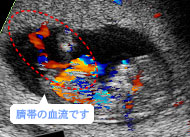

赤と青の帯が血流。母體(tǐ)(胎盤)と胎児は臍帯でつながっているんです。(妊娠12週)

胎児は胎盤を通して母體(tǐ)から栄養と酸素を受け取り、老廃物(wù)を母體(tǐ)に返します。妊娠14~15週に胎盤が完成すると、胎児の生育環境が安定して、発育スピードはアップします。